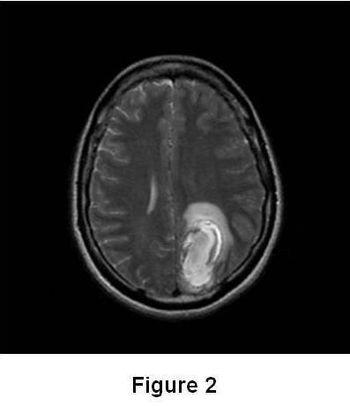

Test your diagnostic knowledge with this month's Image IQ.